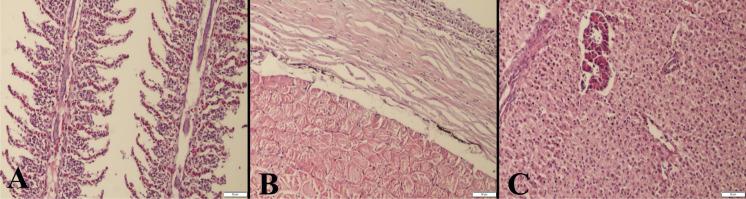

In this study, the anaesthetic effects of fennel and anise essential oils were investigated on common carp. Fish (10 ± 0.45 g) were exposed to nine concentrations of essential oils (5, 10, 20, 50, 100, 200, 300, 400 and 500 mg L). Additionally, the histopathological effects on the fish tissues including gill, skin and hepatopancreas and physiological effects on some blood parameters (Na, K, Ca, Cl, total plasma protein and glucose) of essential oils were investigated in carp. At the end of the experiment, fennel oil showed an anaesthetic effect at a concentration of 500 mg L in carp (anaesthesia induction and recovery times were 308 and 472 s, respectively). Anise essential oil showed deep anaesthesia at a concentration of 100 mg L, but anaesthesia induction time was found to be very long (20 min). In addition, anise oil at concentrations above 100 mg L caused 10% mortality in fish. Blood parameters except glucose level in both essential oils were unchanged during deep anaesthesia in carp. However, plasma glucose levels were found lower in fish anaesthetized with anise oil than control and fennel groups (P < 0.05). At the histopathological examination, no pathological findings were observed in any organ of fish in the fennel group. However, severe hyperemia and inflammatory cell infiltrations in gills, erosive lesions in the skin and slight inflammatory reactions in the skin were observed in the anise group. The present study demonstrated that fennel essential oil at 500 mg L concentration can be used as an effective and safe anaesthetic in common carp, but anise essential oil is not suitable.

在这项研究中,研究了茴香和大茴香精油对鲤鱼的麻醉效果。将鱼(10±0.45g)暴露于九种精油浓度(5、10、20、50、100、200、300、400 和 500mg/L)下。此外,还研究了精油对鱼组织(包括鳃、皮肤和肝胰腺)的组织学影响以及对一些血液参数(Na、K、Ca、Cl、总血浆蛋白和葡萄糖)的生理影响。实验结束时,在鲤鱼中,茴香油在 500mg/L 浓度下表现出麻醉效果(麻醉诱导和恢复时间分别为 308 和 472s)。大茴香精油在 100mg/L 浓度下表现出深度麻醉,但麻醉诱导时间非常长(20 分钟)。此外,在浓度高于 100mg/L 的大茴香油会导致鱼的死亡率达到 10%。在深度麻醉期间,两种精油中的血液参数除葡萄糖水平外均保持不变。然而,与对照组和茴香组相比,用大茴香油麻醉的鱼的血浆葡萄糖水平较低(P<0.05)。在组织病理学检查中,茴香组鱼的任何器官均未观察到病理发现。然而,在大茴香组中,观察到鳃严重充血和炎性细胞浸润、皮肤侵蚀性病变以及皮肤轻微炎症反应。本研究表明,茴香精油在 500mg/L 浓度下可作为鲤鱼的有效和安全麻醉剂,但大茴香精油不适用。